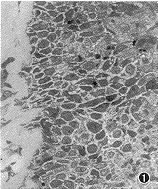

冷冻治疗前鼻粘膜显示典型的慢性肥厚性鼻炎的病理变化,粘膜上皮呈不同程度的鳞状上皮化生、增厚(图1),鳞状化生上皮为多角形或椭圆形,上皮间有许多短的棘状突起,并可见淋巴细胞浸润。固有层结缔组织增生水肿,炎细胞浸润。

图1 冷冻前鼻粘膜光镜观察,上皮增生,鳞状上皮化生(*)。×40